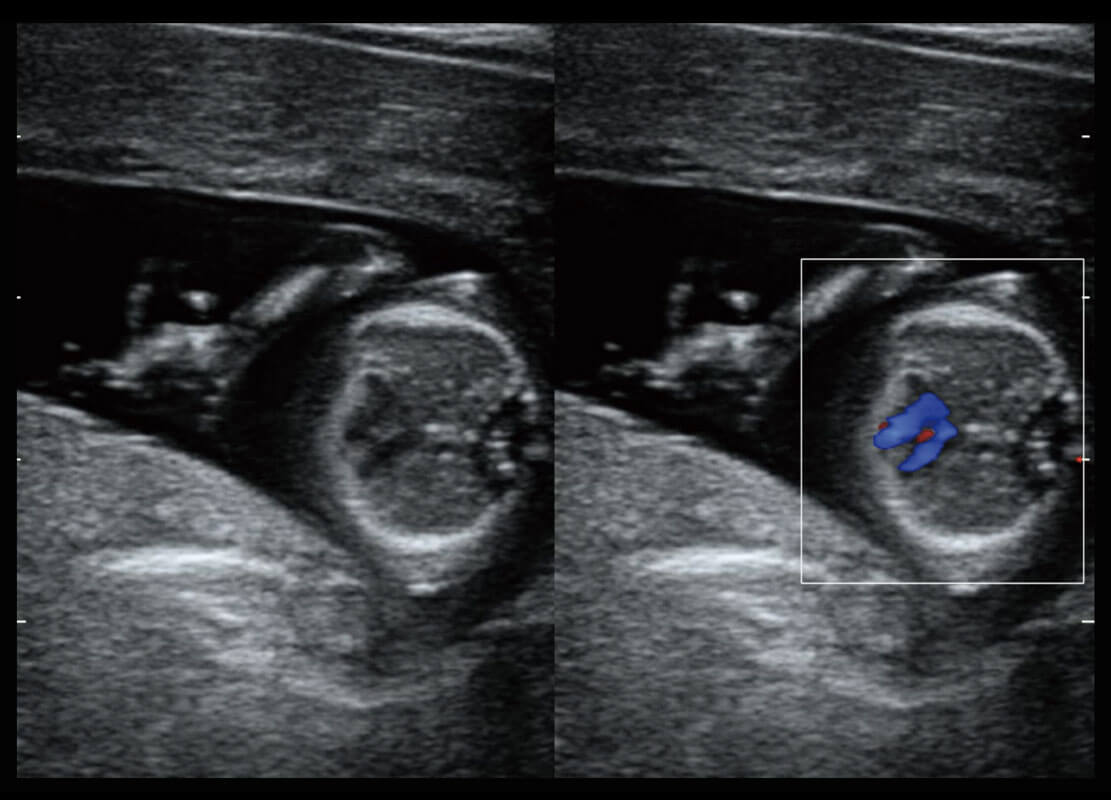

• 四腔切面

• 四腔心血流